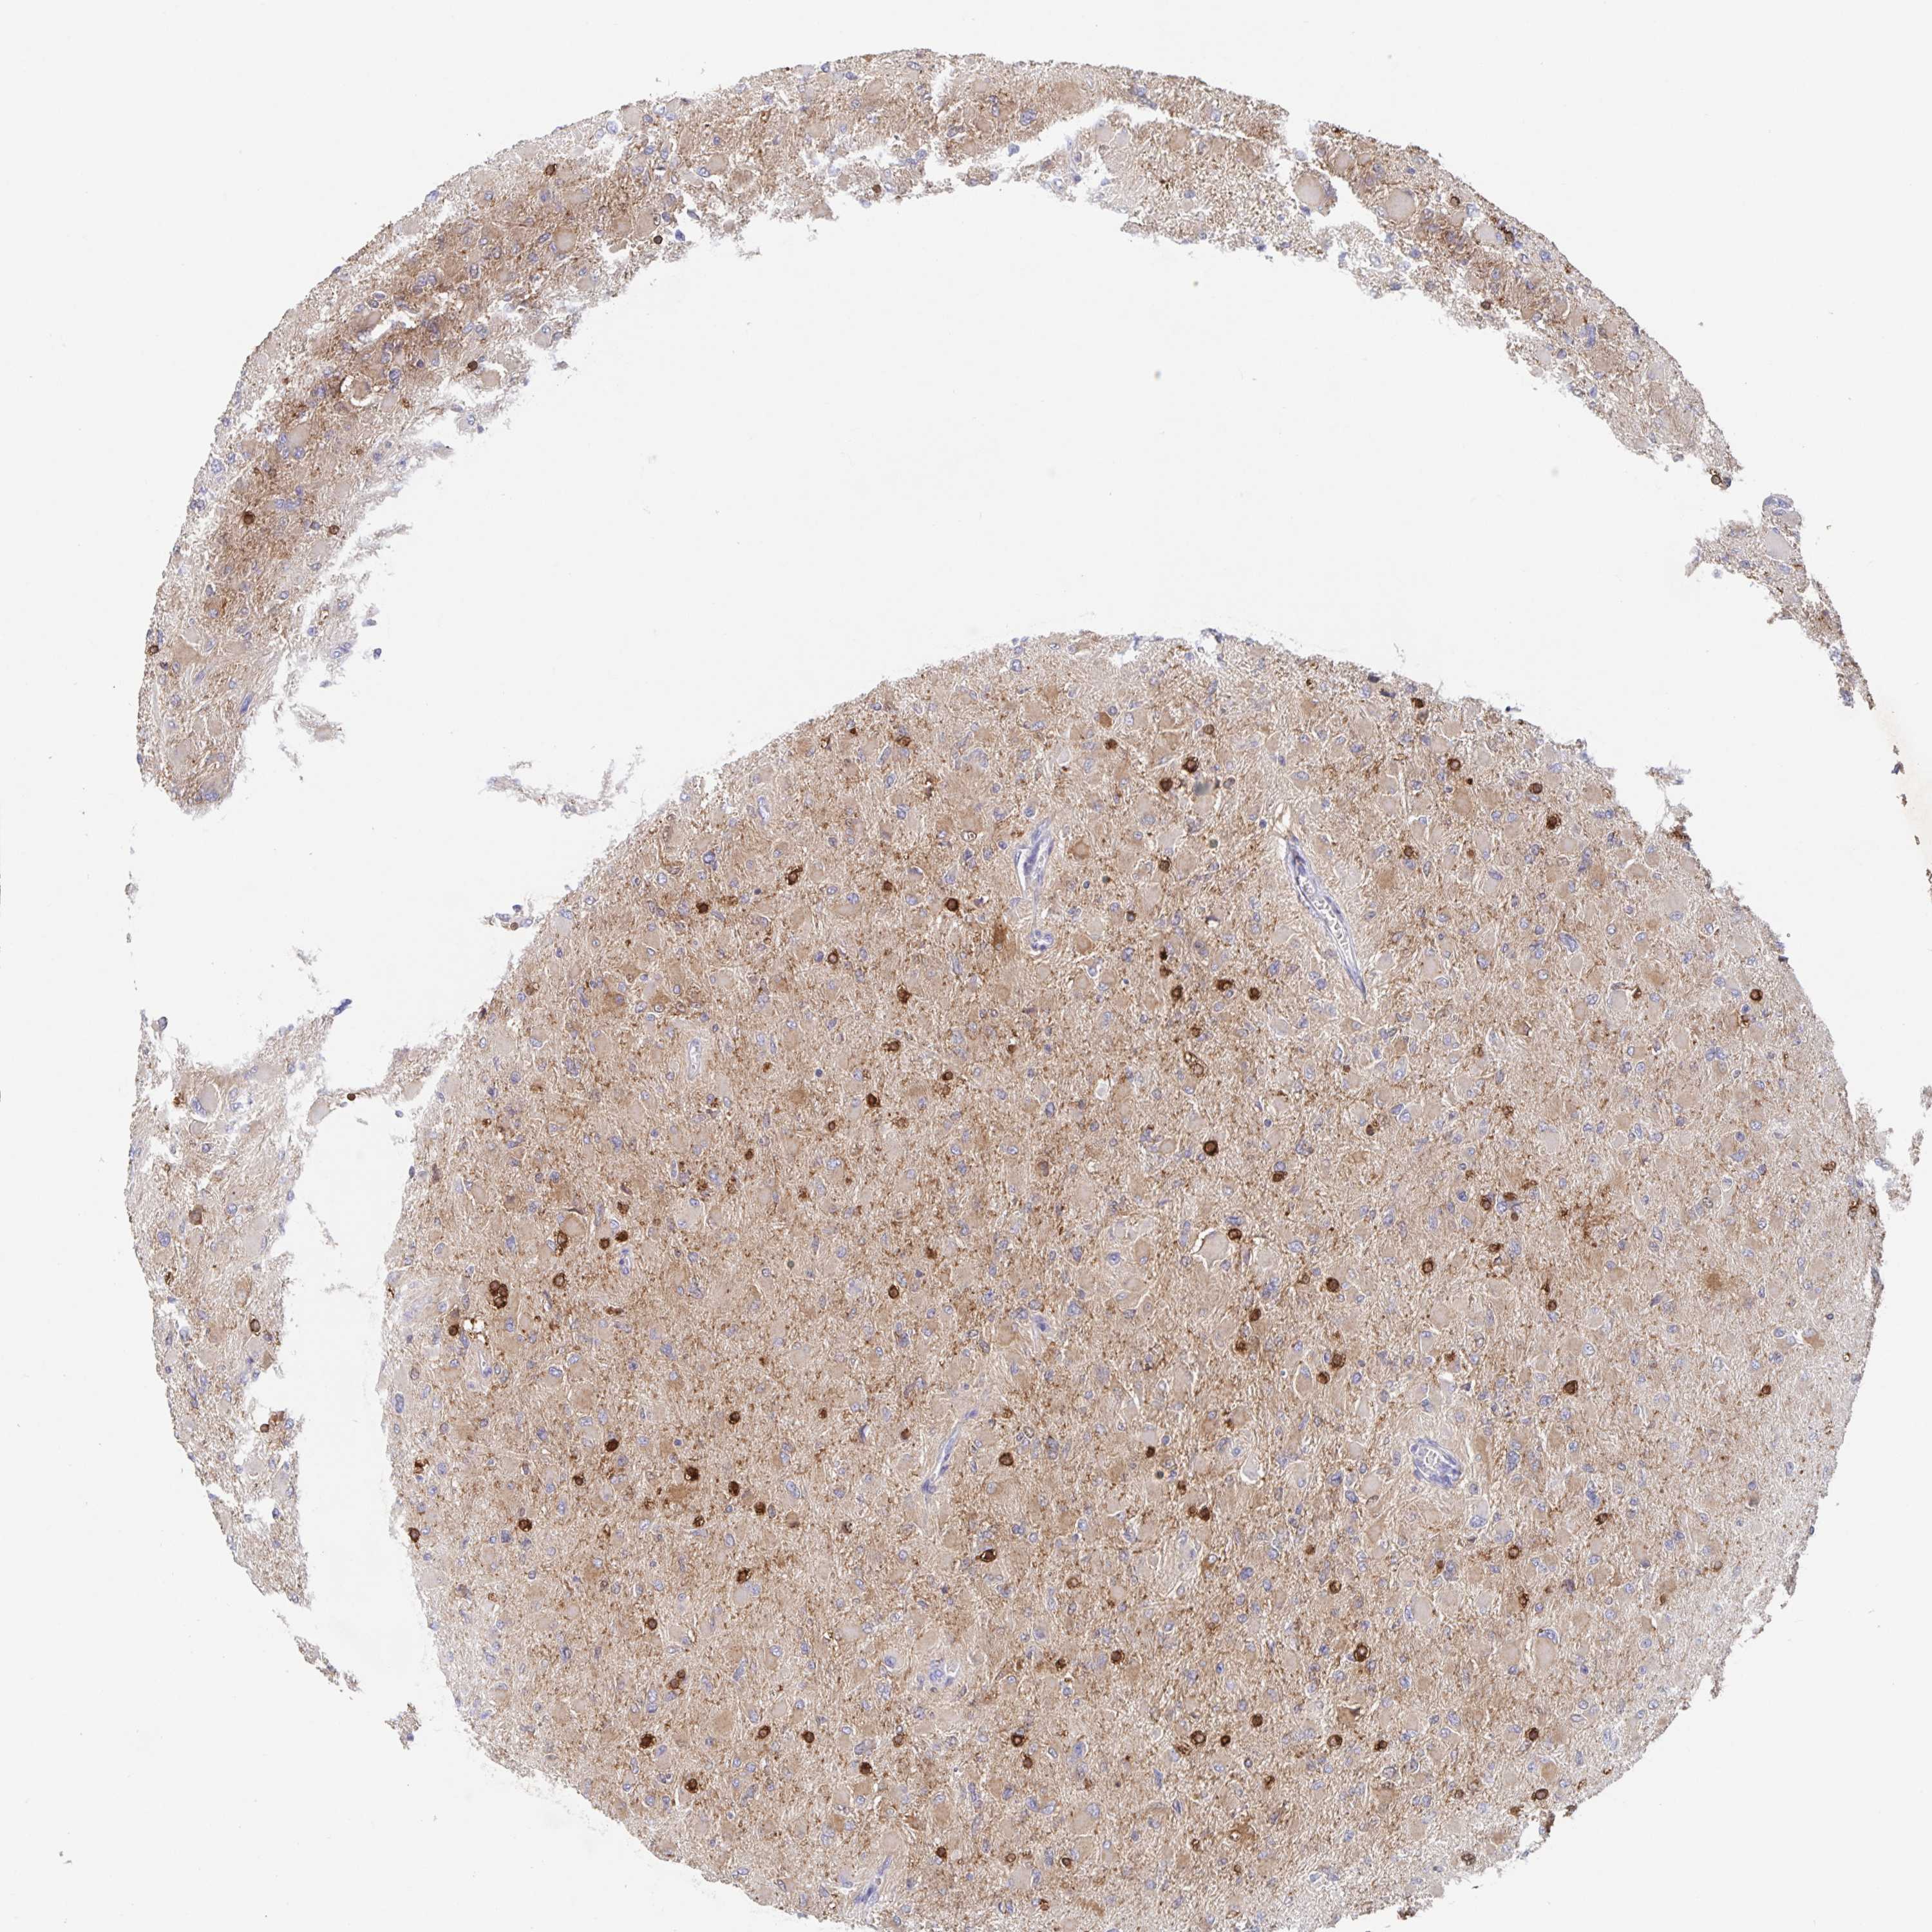

GLIOMA - Protein expressioni

A mouse-over function shows sample information and annotation data. Click on an image to view it in a full screen mode. Samples can be filtered based on level of antibody staining by selecting one or several of the following categories: high, medium, low and not detected. The assay and annotation is described here.

Note that samples used for immunohistochemistry by the Human Protein Atlas do not correspond to samples in the TCGA dataset.

Antibody stainingi

Antibody staining in the annotated cell types in the current human tissue is reported as not detected, low, medium, or high, based on conventional immunohistochemistry profiling in selected tissues. This score is based on the combination of the staining intensity and fraction of stained cells.

Each image is clickable and will lead to virtual microscopy that enables deeper exploration of all samples and also displays staining intensity scores, fraction scores and subcellular localization as well as patient and tissue information for each sample.

Antibody HPA027382

Antibody HPA061836

Staining

High

Medium

Low

Not detected

Intensity

Strong

Moderate

Weak

Negative

Quantity

>75%

75%-25%

<25%

None

Location

Nuclear

Cytoplasmic/membranous

Cytoplasmic/membranous,nuclear

Glioma, malignant, High grade

Glioma, malignant, Low grade